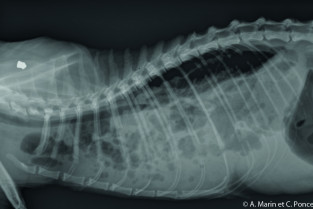

Avant lors d'affection thoracique, seule la radiographie était facilement à accessible au praticien, malgré les difficultés de lecture et d'interpétation. Un tour d'horizon des affections bronchopulmonaires, pleurales et extrapleurales et des autres méthodes d'imagerie utilisables sera envisagé grâce à un duo médecin/imageur.

- d'interpréter les radiographies thoraciques normales ;

- citer les indications de l'échographie lors d'affection thoracique ;

- d'appréhender une affection pleurale /extra pleurale ;

- d'appréhender une affection broncho-pulmonaire.